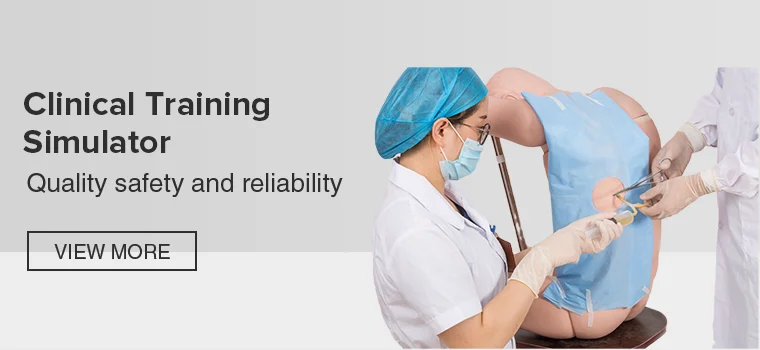

19YRSMain categories: Emergency training manikin,Physical examination training simulator,Nursing skills training simulator,Clinical skills training simulator,Maternal and infant training simulator